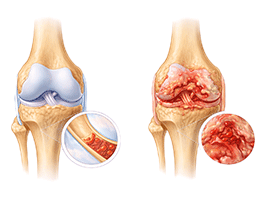

골관절염 (Osteoarthritis)

류마티스 관절염 (Rheumatoid Arthritis)

통풍 (Gout)